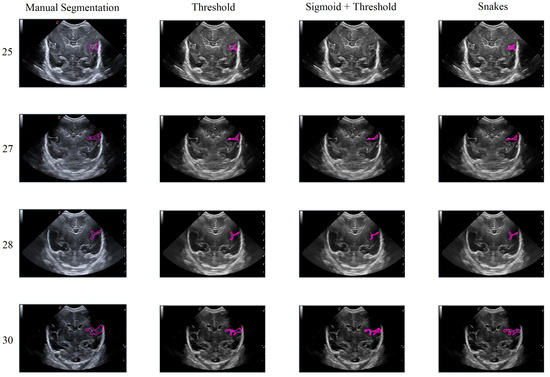

In this section, the limitations and considerations were discussed. Each of the three segmentation methods has its own advantages and drawbacks. However, there is a potential loss of precision in defining the shape of the groove, both in its actual form and during the segmentation process. Additionally, ultrasound noise can impact the accuracy of the segmentation, making some methods less suitable. Figure 18 illustrates how imprecise manual segmentation affects the effectiveness of the Threshold and Sigmoid + Threshold methods, while these methods yield satisfactory results when the manual segmentation is more precise. Conversely, the Snake method remains unaffected by the segmentation approach and consistently provides satisfactory results.

Figure 18. Example of how the segmentation results vary with different methods depending on the accuracy of the manual segmentation, with the first row showing more precise manual segmentation and the second row showing less precise manual segmentation.